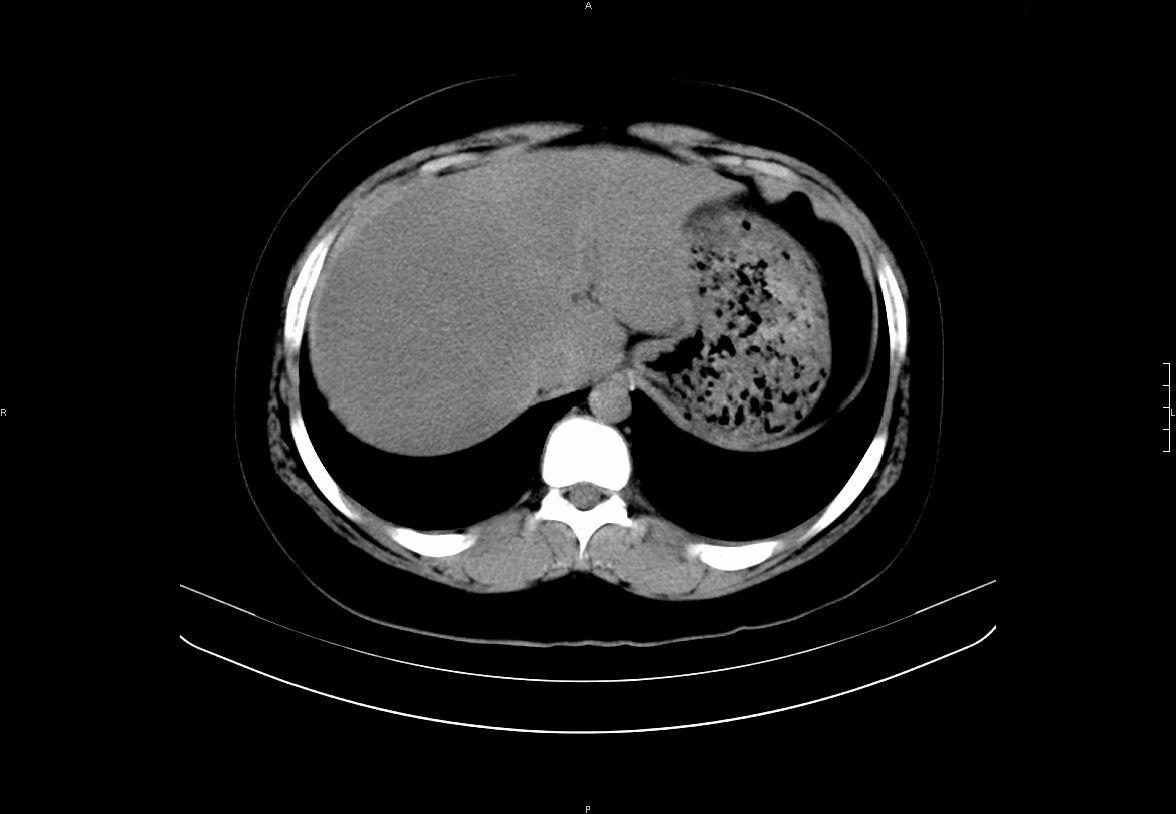

增强:

增强动脉期前述低密度区轻度早其强化,门脉期强化程度显著增高,延期扫描强化程度下降,但仍为相对高密度影

2左肝及右肝前叶表现考虑胆囊摘除术后所致的肝动门脉瘘形成,慢性纤维组织炎性增生.不完全除外左肝胆管细胞癌

考虑:1、胆道结石伴肝内胆管扩张、积气;胆系感染!2、从平扫、增强片来看,不存在胆管肿瘤征象;3、提介建议:作为影像医师,在做一项检查之前应先熟悉临床医生的目的,象这个病例,检查前就不应喝高密度造影剂,而应充分喝好水就可,要不适得其反,反而较难判断胆总管下段是否有结石。

1)肝内胆管结石,胆总管末端结石伴肝内胆管扩张。2)肝左叶及肝右叶前段增强前后之异常表现,考虑炎性改变,不排除胆管细胞癌。